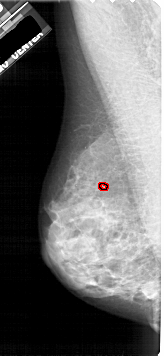

A_1914_1.RIGHT_CC

RIGHT_CC LINES 5041 PIXELS_PER_LINE 2446 BITS_PER_PIXEL 12 RESOLUTION 43.5 NON_OVERLAY

FILE: A_1914_1.LEFT_MLO.OVERLAY

TOTAL_ABNORMALITIES 1

ABNORMALITY 1

LESION_TYPE CALCIFICATION TYPE PLEOMORPHIC DISTRIBUTION CLUSTERED

ASSESSMENT 4

SUBTLETY 2

PATHOLOGY BENIGN

TOTAL_OUTLINES 1

BOUNDARY